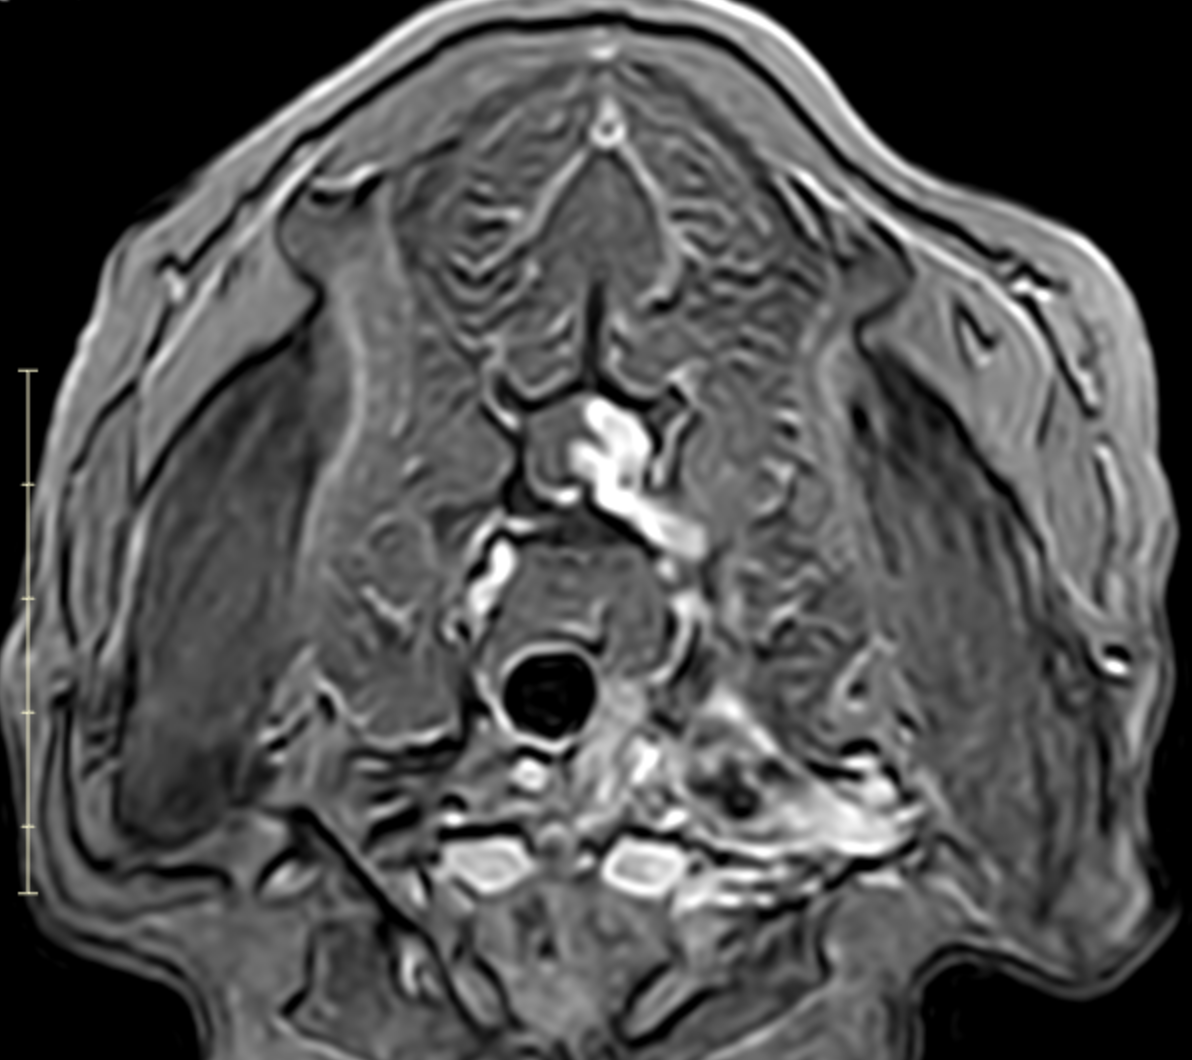

Image 7. Transverse post-contrast MRI showing asymmetric enlargement and contrast enhancement of the left C7–T1 nerve roots with associated spinal cord displacement, consistent with a nerve sheath tumor.

MRI revealed a clinically significant and previously undetected diagnosis (Images 5-7):

Primary Diagnosis: Nerve Sheath Tumor

• Contrast-enhancing mass involving the left C7, C8, and T1 nerve roots

• Extension from the spinal canal through the intervertebral foramen into the axilla and brachial plexus

• Severe spinal cord compression with displacement

• Expansion of the C7–T1 neural foramen

• Associated neurogenic muscle atrophy of the left forelimb (triceps)